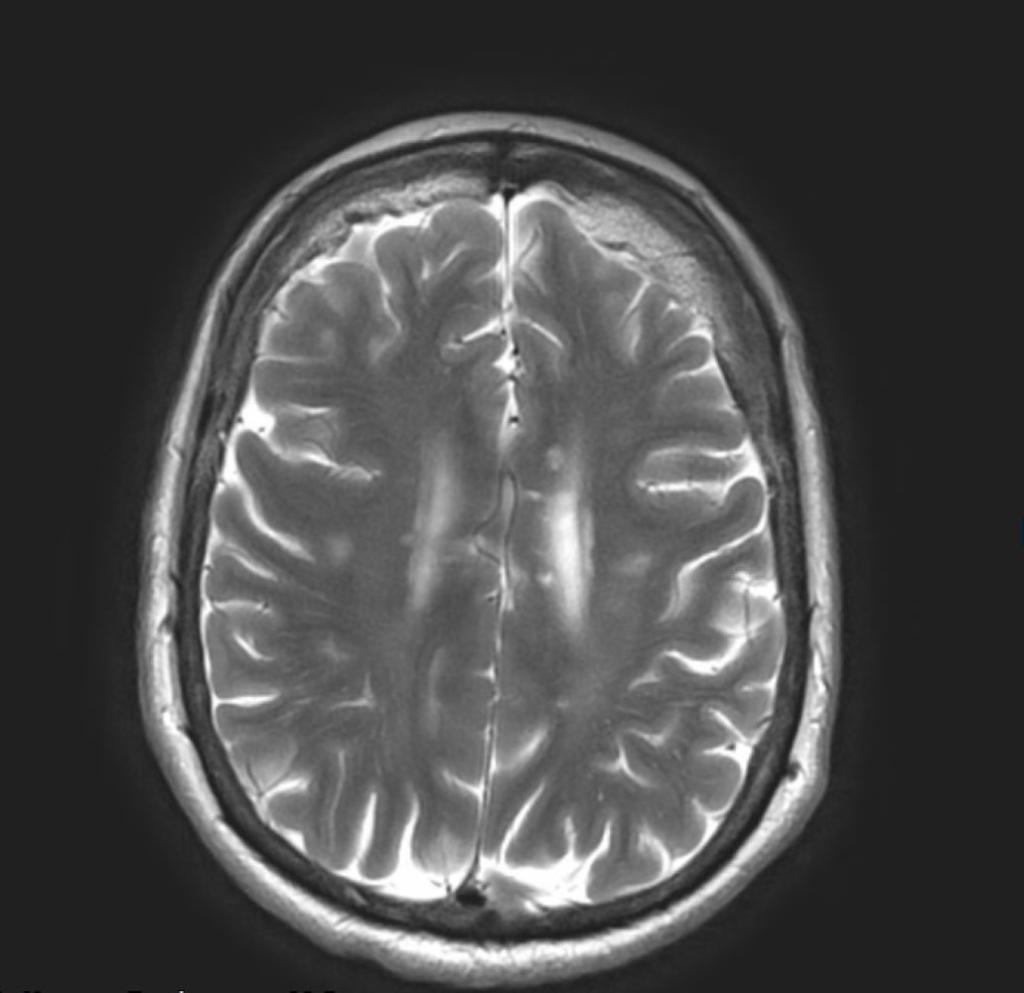

Gepubliceerd: Week 07 - 2024 711 deelnemers Je ziet een 35-jarige vrouw op je spreekuur met een bont scala aan klachten. Ze doen je denken aan het syndroom van Susac, een zeldzame auto-immuunangiopathie. Welke trias doet je aan deze diagnose denken? Antwoord Proteïnurie, hypoalbuminemie en oedemen. Encefalopathie, retinopathie en gehoorverlies. Icterus, nierfalen en verhoogde bloedingsneiging. Oftalmoplegie, areflexie en ataxie. Antwoord controleren